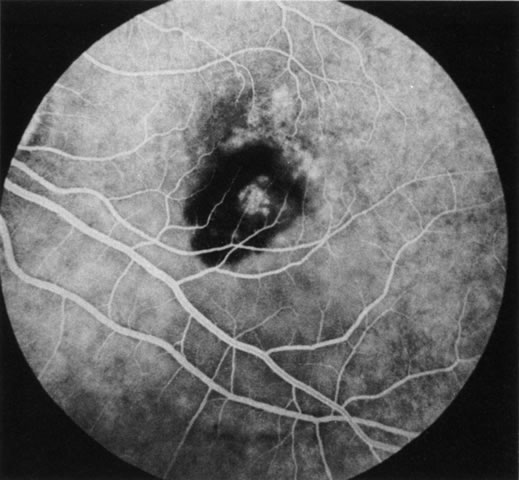

FA is also useful in characterizing two other subgroups of CNV: retinal angiomatous proliferation (RAP)8–16 and polypoidal choroidal vasculopathy (PCV).17–50 RAP begins in the deep retinal complex, forming intraretinal neovascularization (IRN), which may subsequently progress to extend beneath the neurosensory retina, forming subretinal neovascularization (SRN), and a vascularized PED.8 In the later phases of the process there may be a retinal-choroidal anastomosis (RCA). Clinical features of RAP include intraretinal hemorrhages, cystoid macular edema, and associated vascularized PED. FA is useful in revealing the presence of the angiomatous intraretinal vascular complex and the extension of the associated PED (Figs. 12 and 13). However, other diagnostic techniques such as indocyanine green (ICG) angiography, and optical coherence tomography (OCT) may be able to better demonstrate the presence of the RAP lesion.

Fig. 12. A. Clinical photograph of a retinal angiomatous proliferation (RAP) lesion (arrow). Note the intraretinal angiomatous proliferation, a feeding retinal arteriole, and a draining retinal venule, as well as the presence of intraretinal hemorrhages. B–C. Fluorescein angiography reveals late leakage from the RAP lesion.